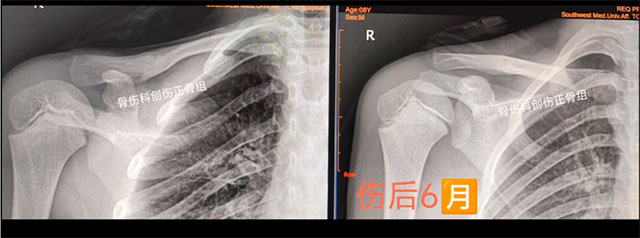

8岁的乐乐同样也是玩耍时不慎摔伤导致右锁骨骨折,来到骨伤科创伤·正骨组就诊,王念武医生同样采用中医正骨手法,小夹板固定治疗,3个月骨折愈合,功能也完全恢复。

术前

术后

根据骨折与脱位的具体情况,进行骨折手法整复,选好适当的小夹板、绷带、棉垫和束带等材料,充分配合骨伤科特制的中药制剂内服及外用治疗,具有复位过程快、固定效果好、疼痛缓解迅速、康复时间短、治疗费用低等优势。